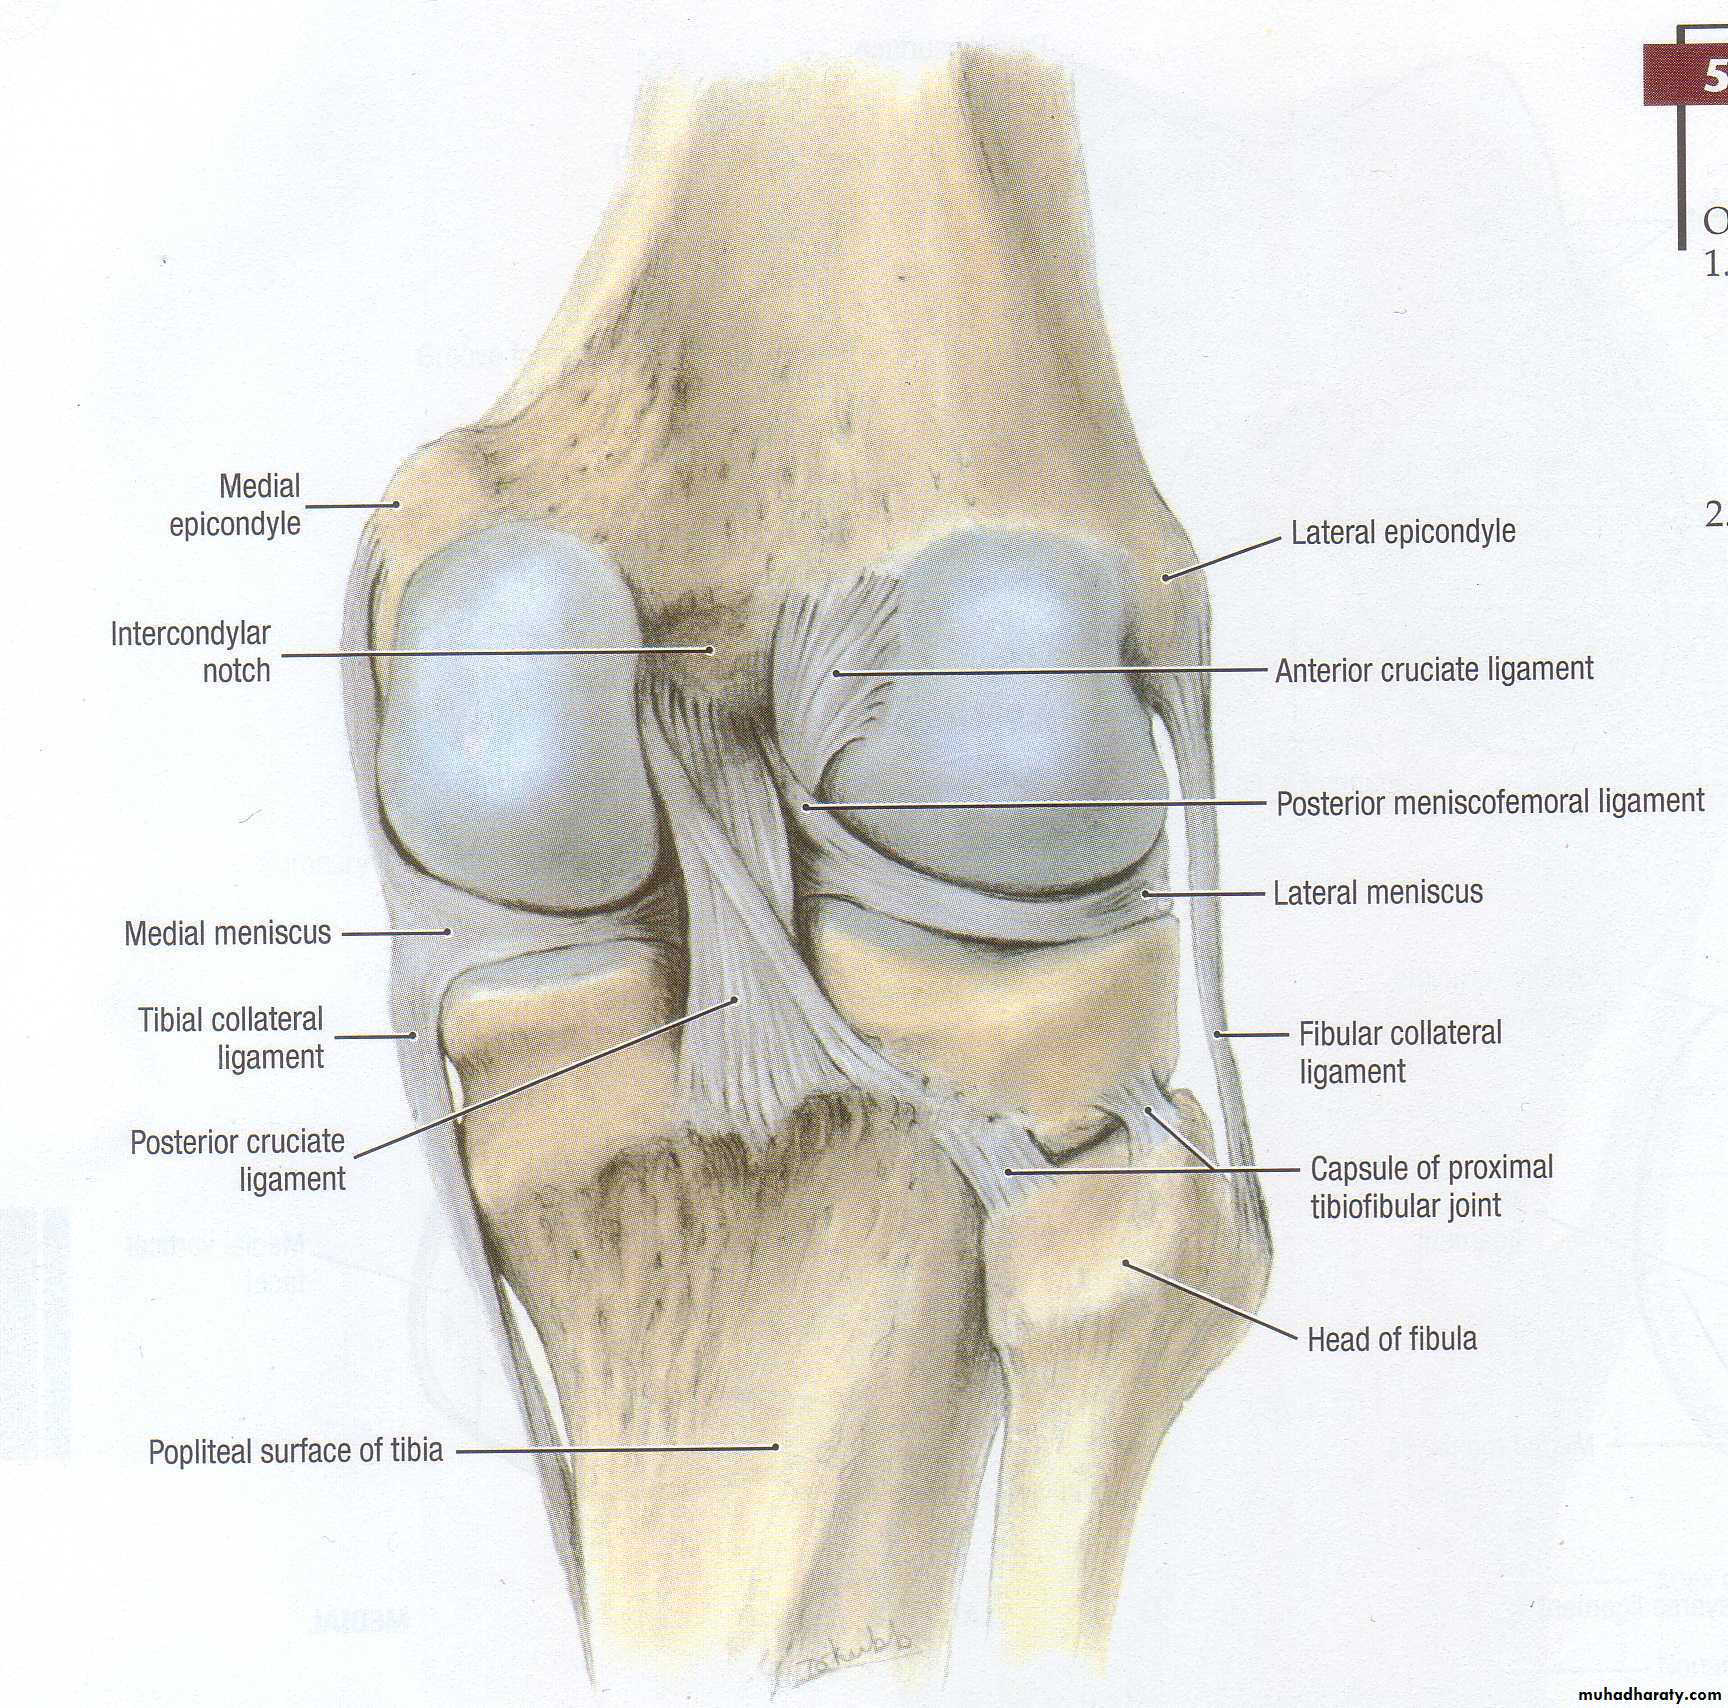

9Meniscal injuries

Functions

Improve stability

Load distribution

Increase range of motionProprioception

Pathology

Medial meniscus is less mobile more liable for injuryMost of the meniscus is avascular : tear not capable of healing except the lateral third